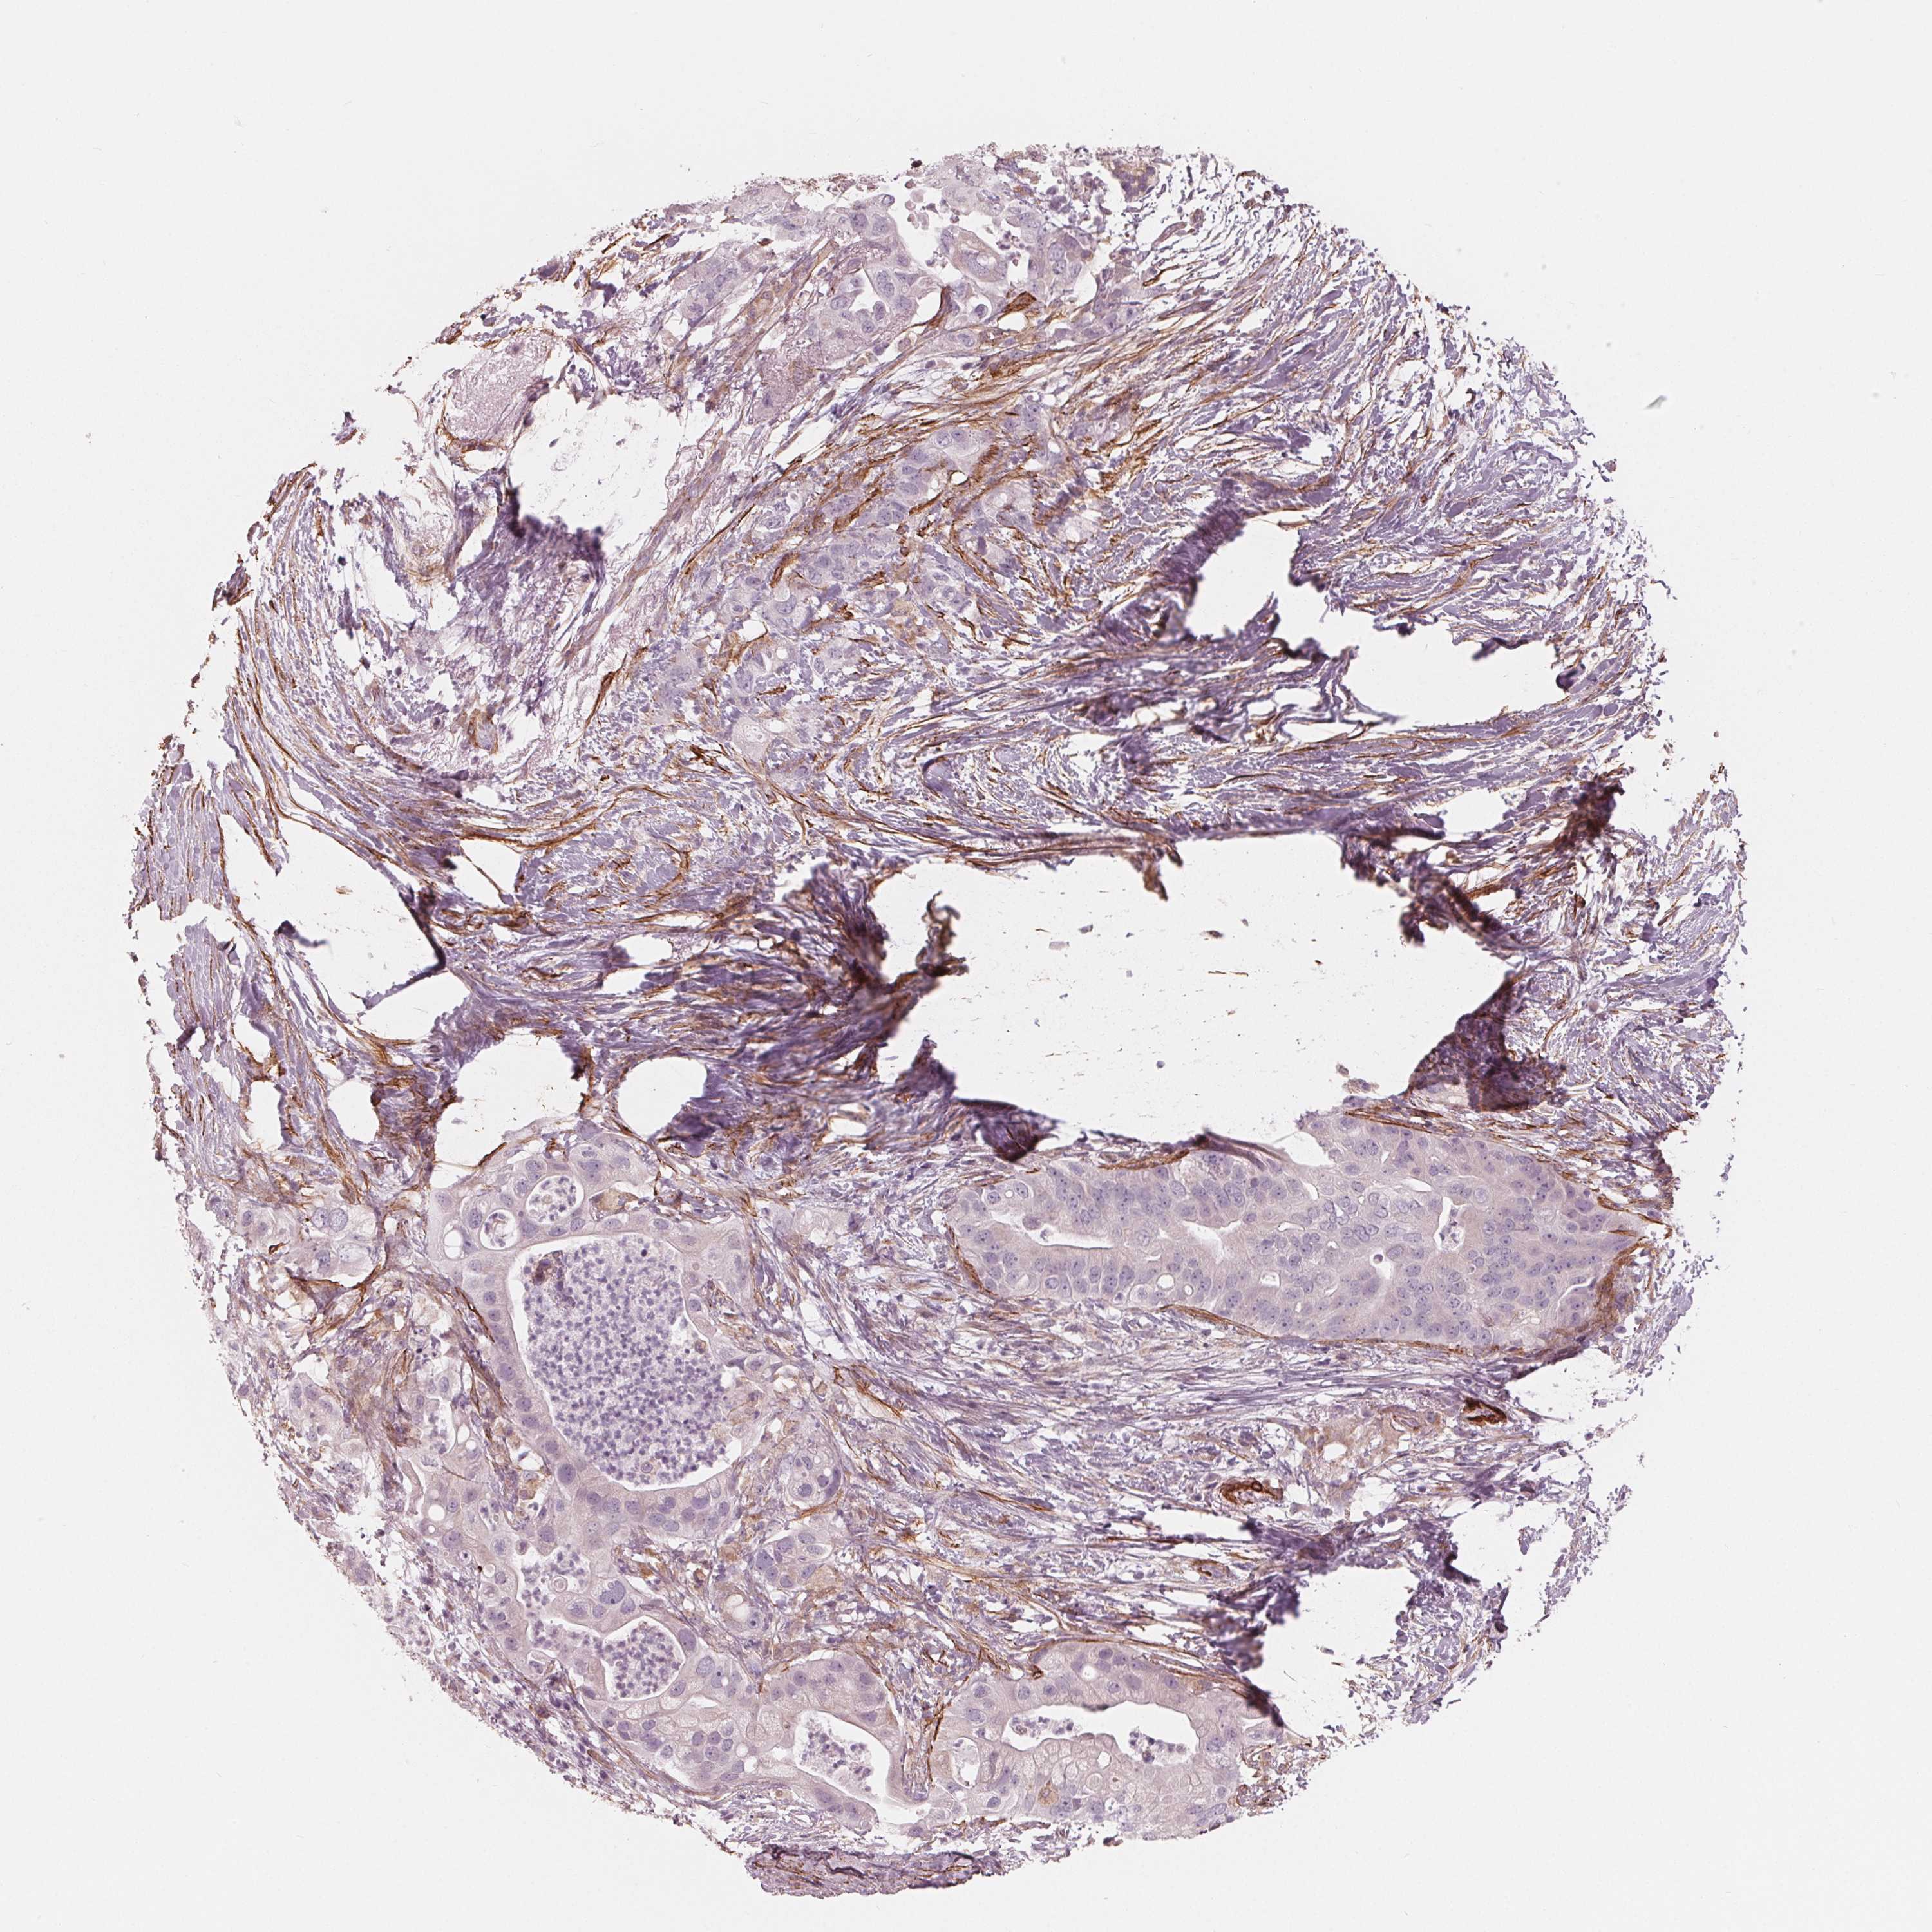

PANCREATIC CANCER - Protein expressioni

A mouse-over function shows sample information and annotation data. Click on an image to view it in a full screen mode. Samples can be filtered based on level of antibody staining by selecting one or several of the following categories: high, medium, low and not detected. The assay and annotation is described here.

Note that samples used for immunohistochemistry by the Human Protein Atlas do not correspond to samples in the TCGA dataset.

Antibody stainingi

Antibody staining in the annotated cell types in the current human tissue is reported as not detected, low, medium, or high, based on conventional immunohistochemistry profiling in selected tissues. This score is based on the combination of the staining intensity and fraction of stained cells.

Each image is clickable and will lead to virtual microscopy that enables deeper exploration of all samples and also displays staining intensity scores, fraction scores and subcellular localization as well as patient and tissue information for each sample.

Antibody HPA065946

Staining

High

Medium

Low

Not detected

Intensity

Strong

Moderate

Weak

Negative

Quantity

>75%

75%-25%

<25%

None

Location

Nuclear

Cytoplasmic/membranous

Cytoplasmic/membranous,nuclear

Adenocarcinoma, NOS